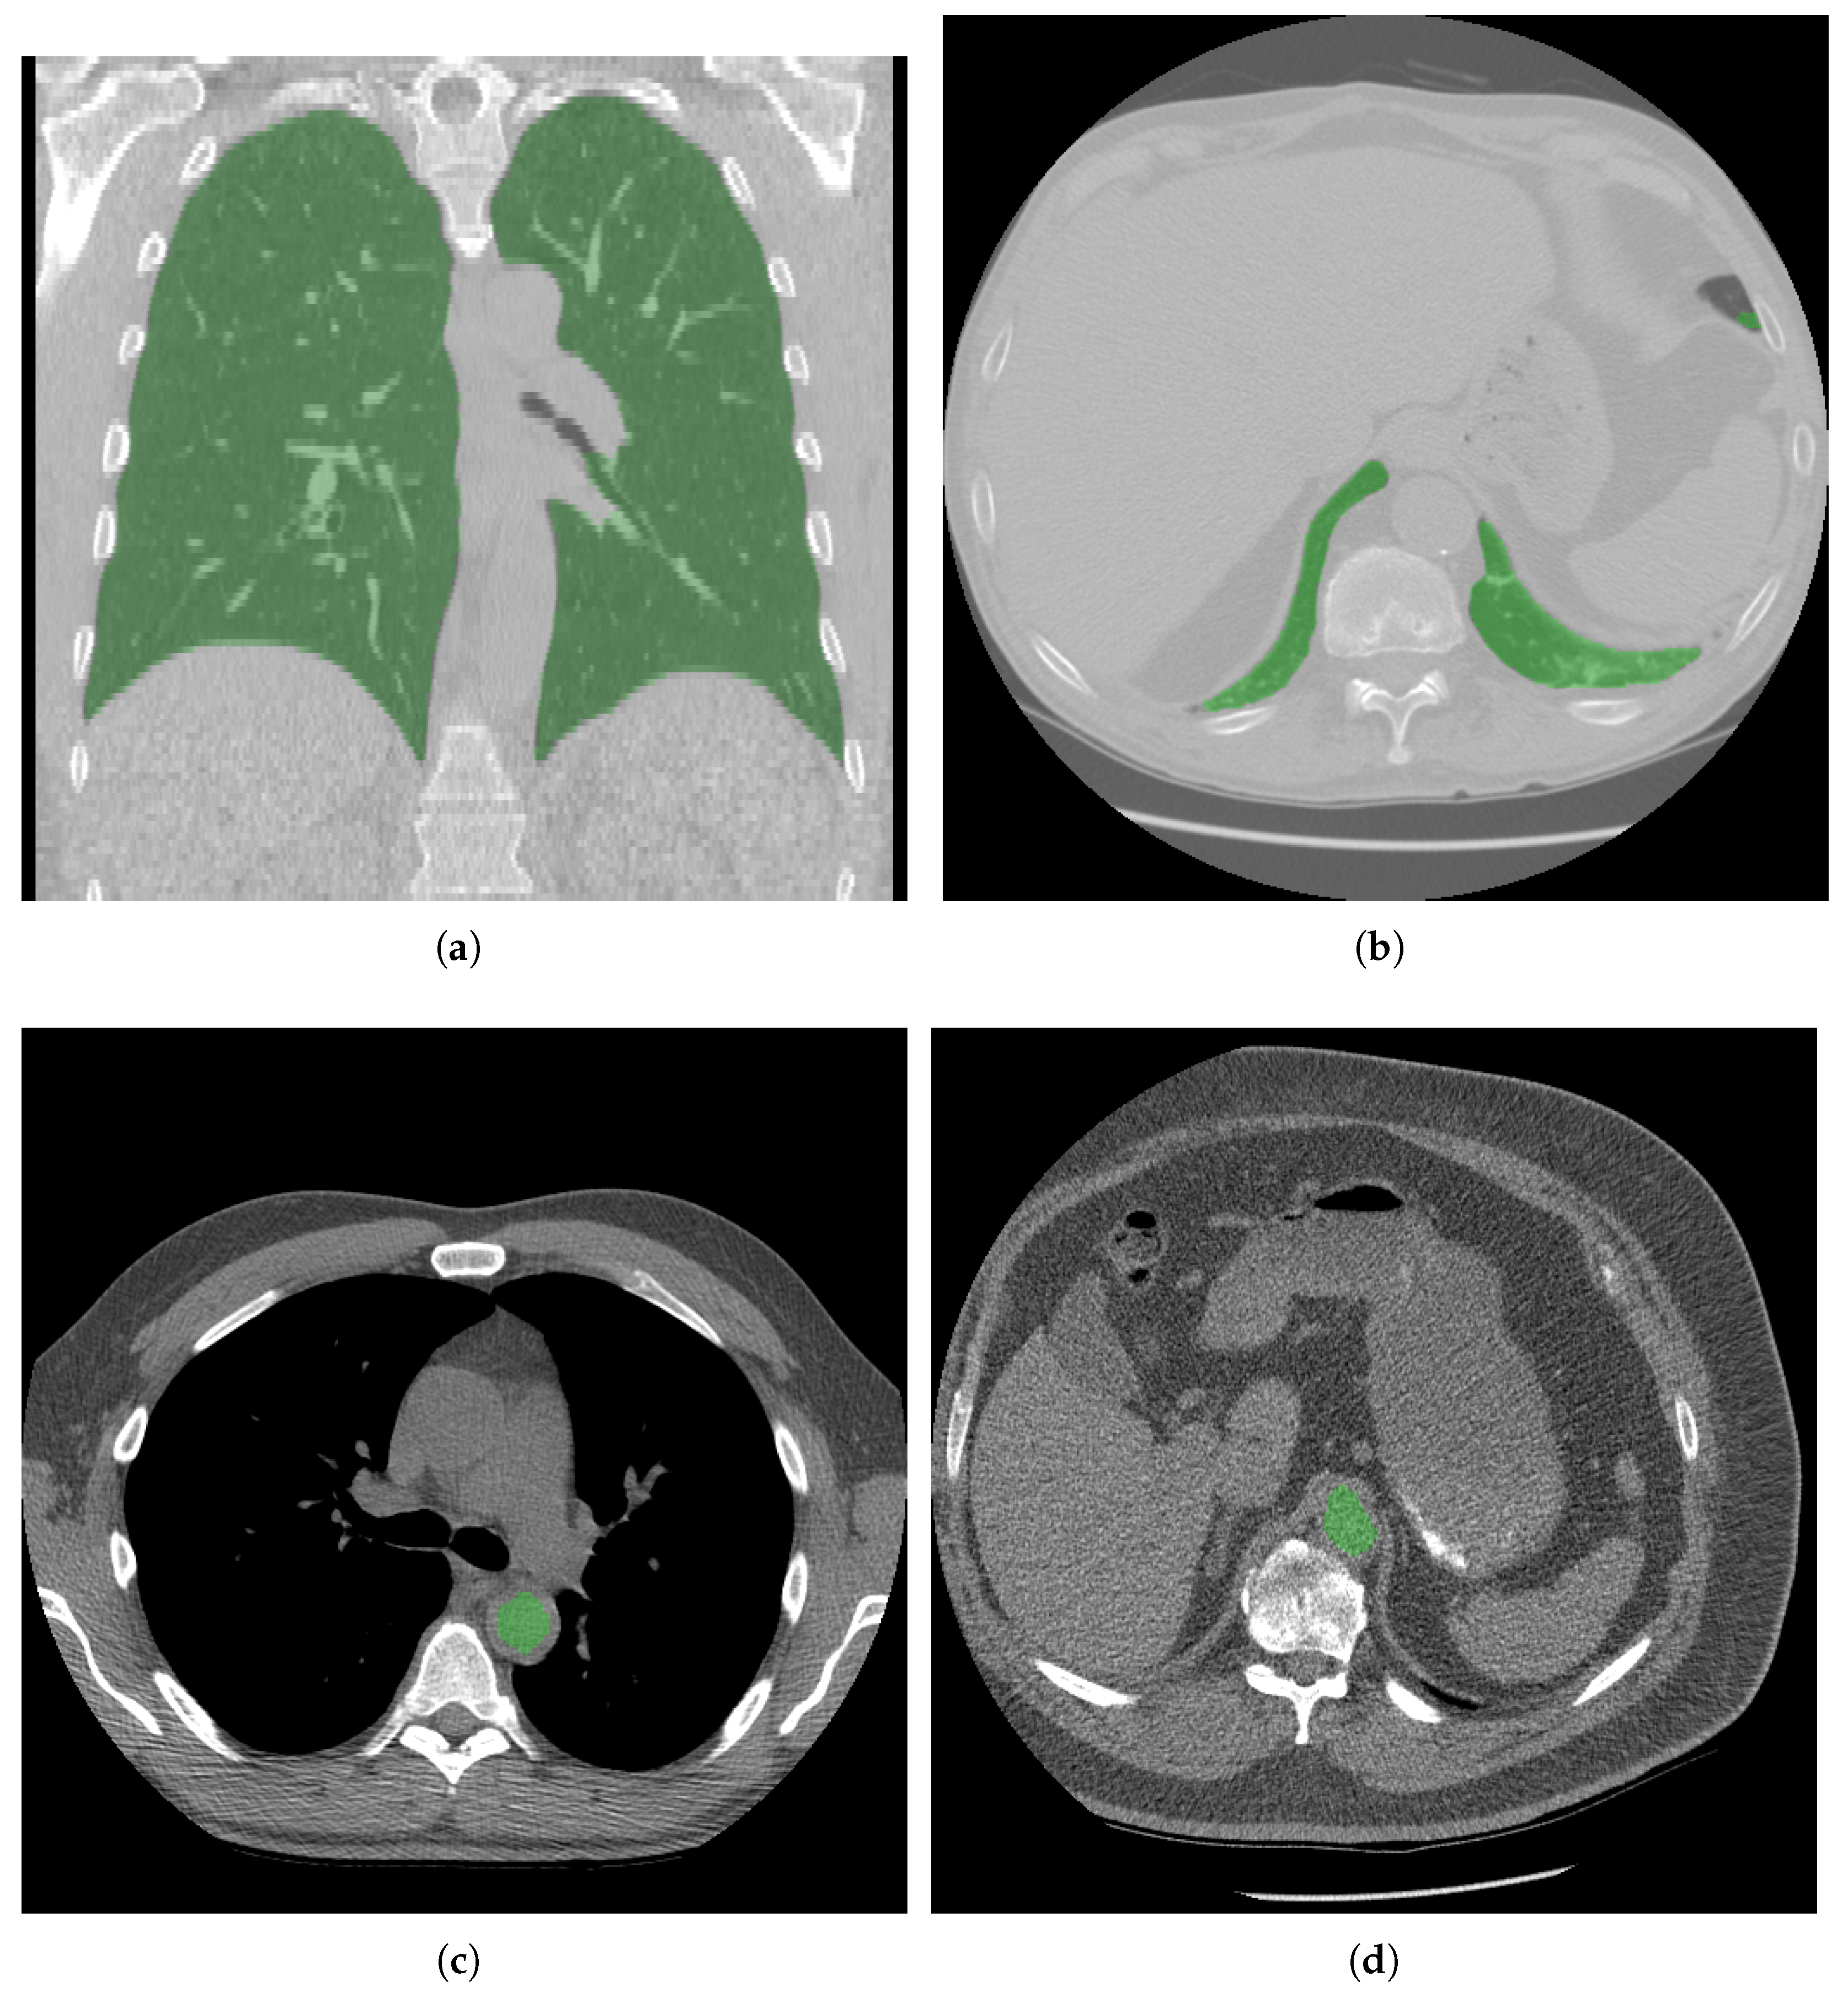

3.1. Over- and Underscanning

3.2. Noise Calculation